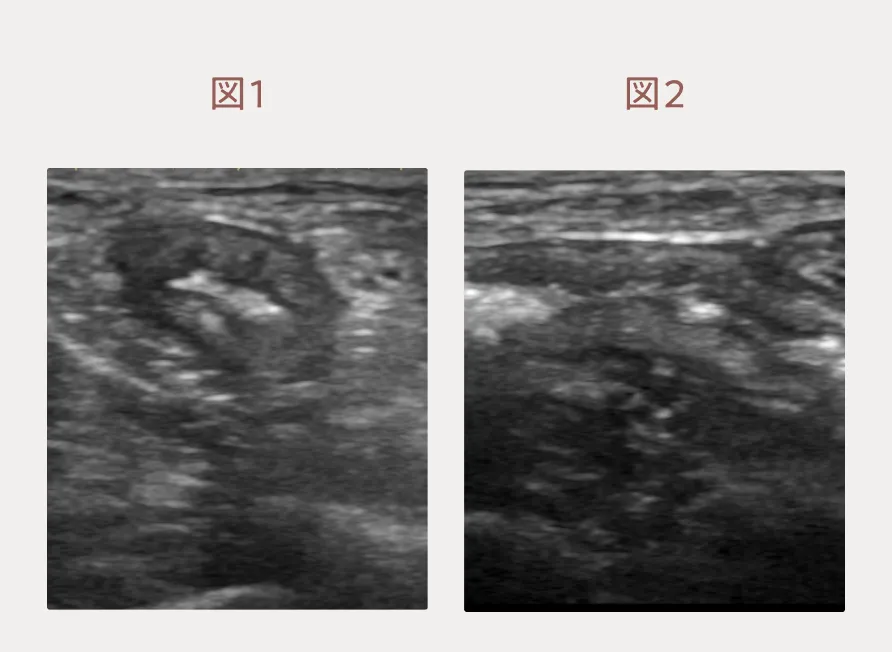

血液検査では特筆すべき異常所見はありません。一方、エコー検査では大腸の短さと大腸壁の肥厚(特に粘膜下織の肥厚)を感じました(図1:短軸、図2:長軸)。小腸も腸壁の肥厚があり、短結腸症候群とびまん性胃腸疾患(慢性腸炎やリンパ腫など)の併発を疑い、内視鏡検査を推奨しました。